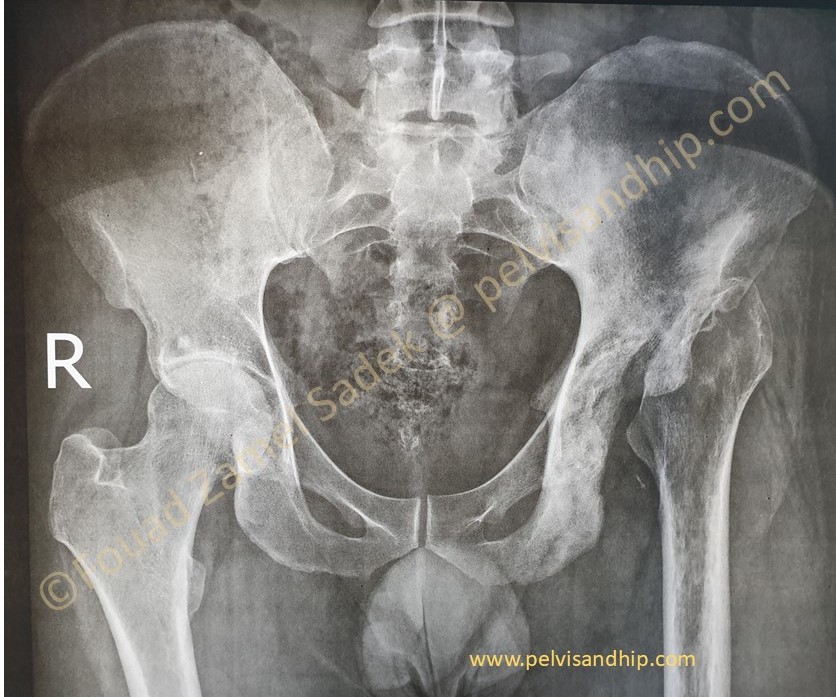

A 34 years old male with a two years history of previous infections related to the left hip and pelvis. Previous surgical interventions to clear infection carried out more than a year ago with no obvious recurrence of infective related issues. Note that he also has arthritic changes on the right hip as well.

At presentation, clinically infection was cleared and inflammatory profiles are all normal. Patient coming asking to have a joint replacement for better function and improvement of quality of life. He is only able to mobilize with crutches and foot can barely touch the ground. He is not able to work in his current status.

The obvious leg length discrepancy on the left side. The scar of previous interventions suggest some lateral based surgical approach which is well healed with no obvious suspicion of active inflammation.